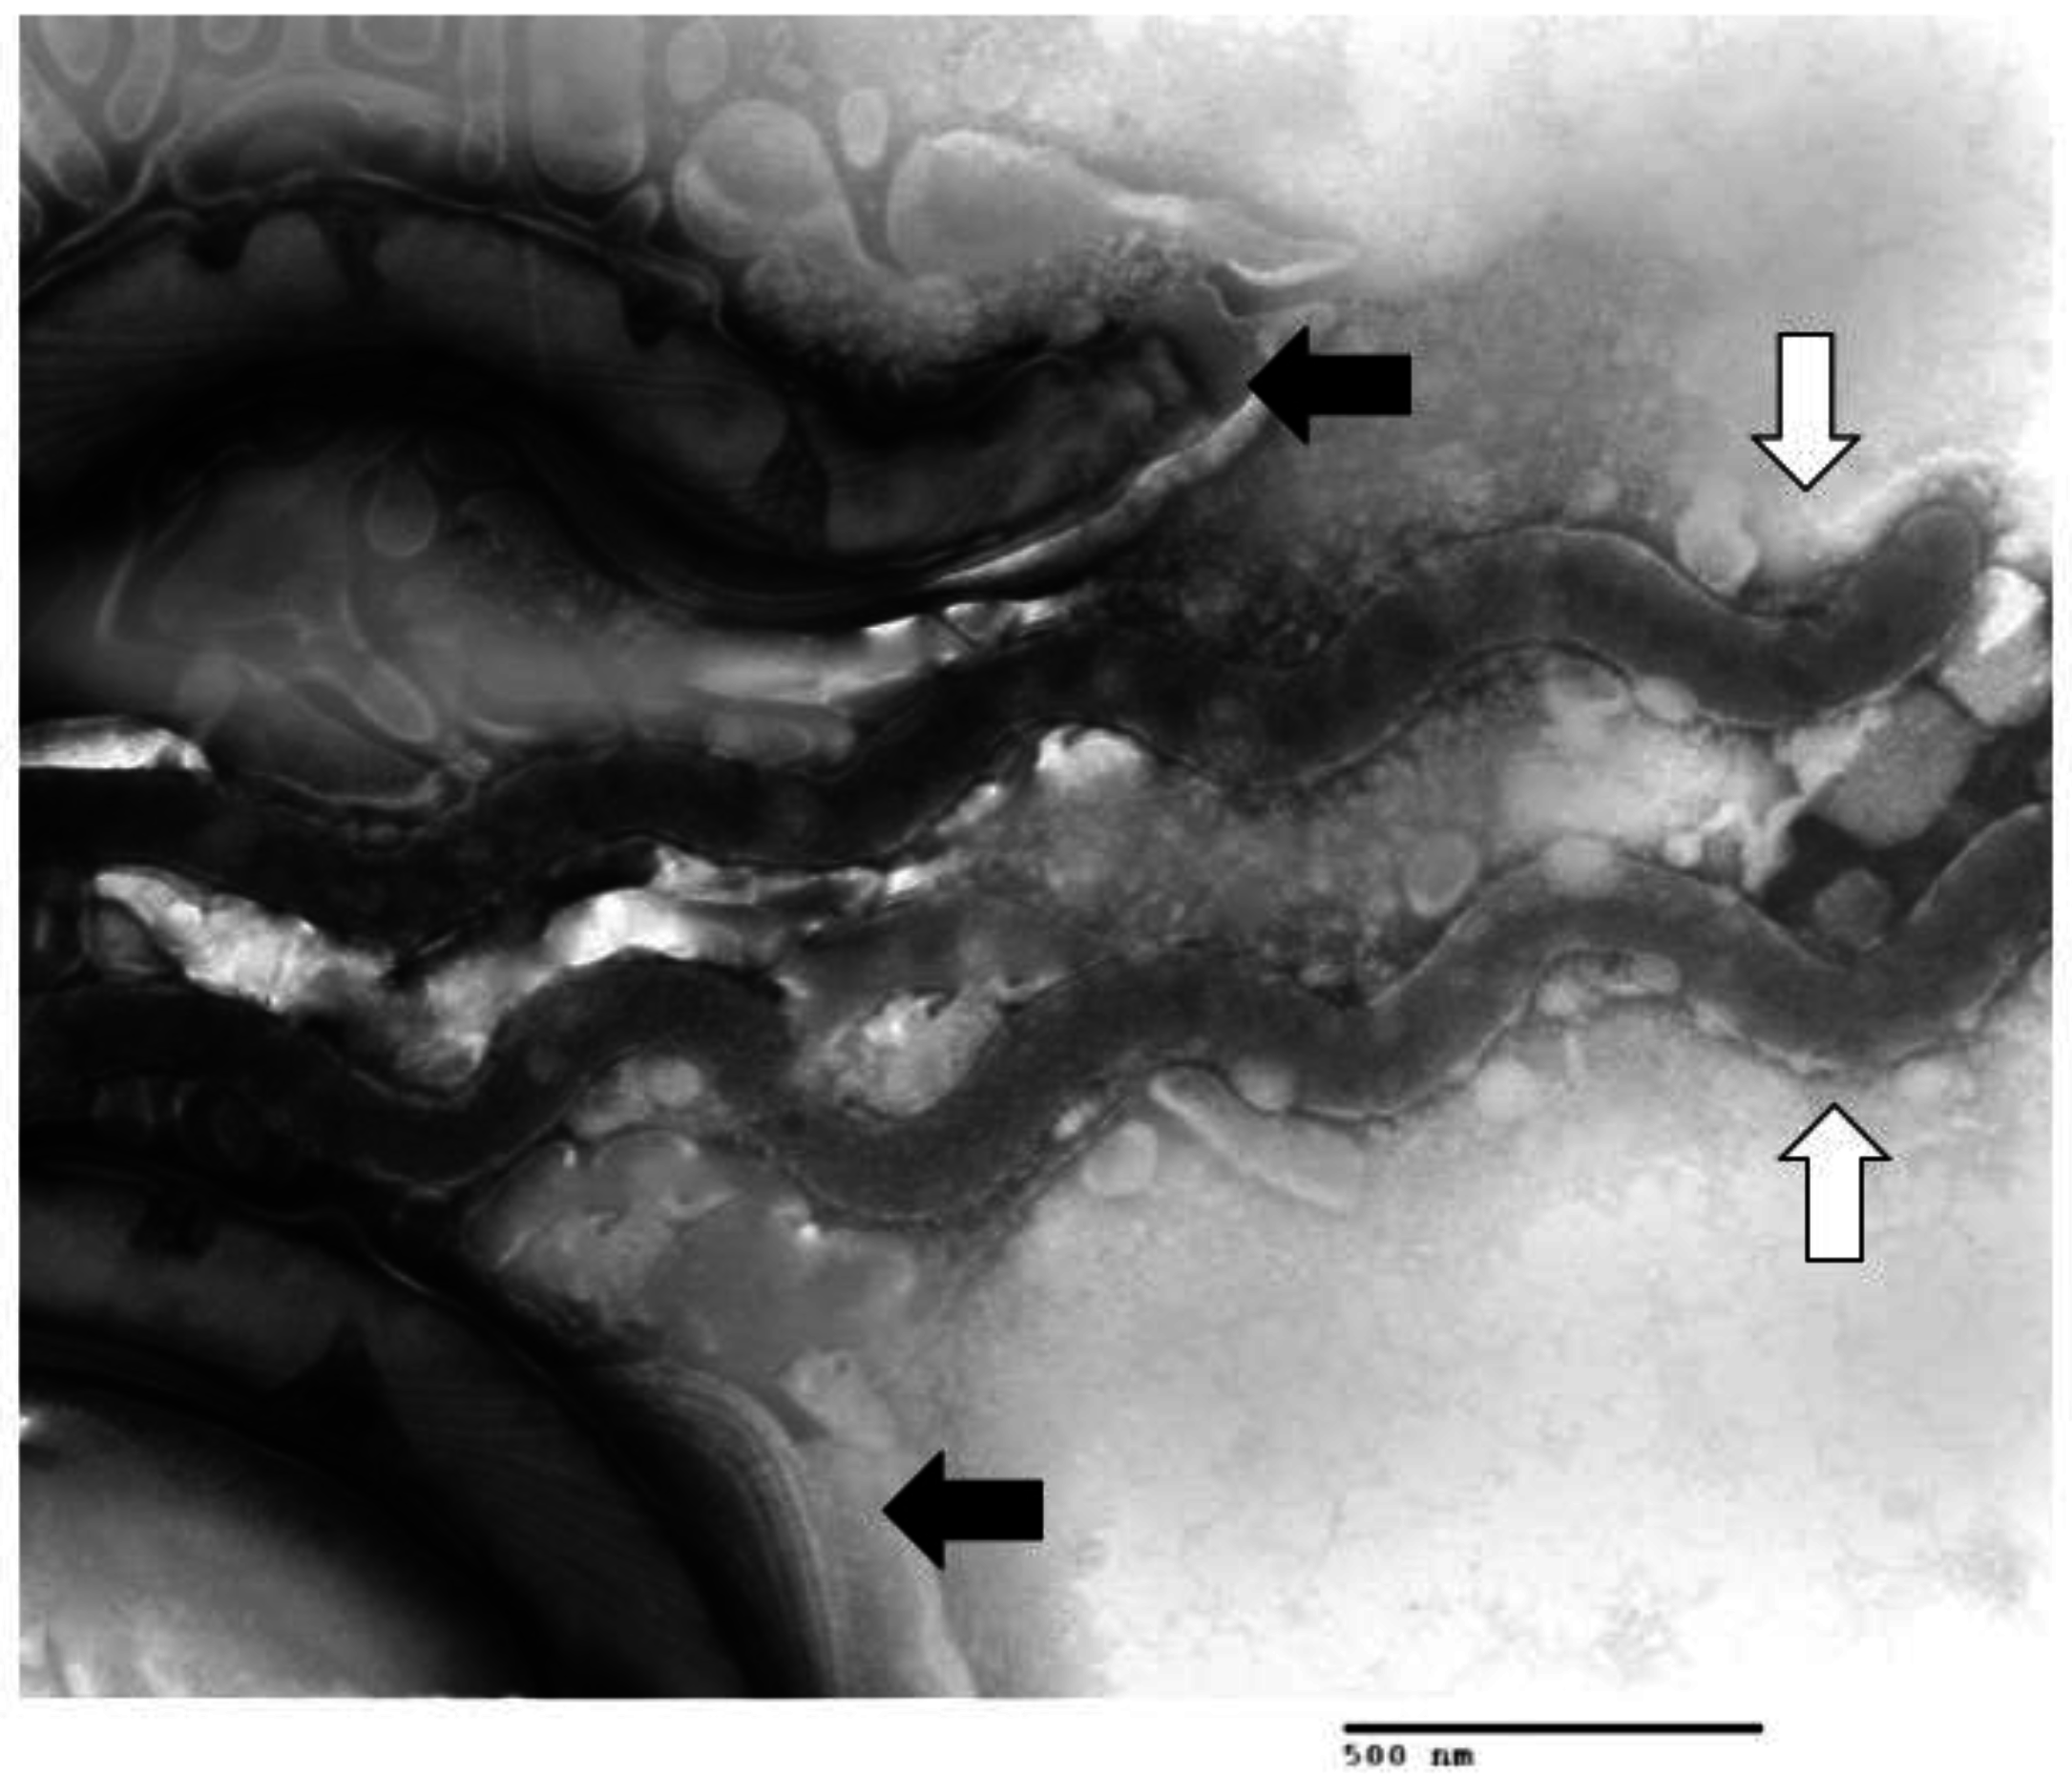

1.2. Multiple Treponema Associated with DD

1.3. Other Bacteria Associated with DD